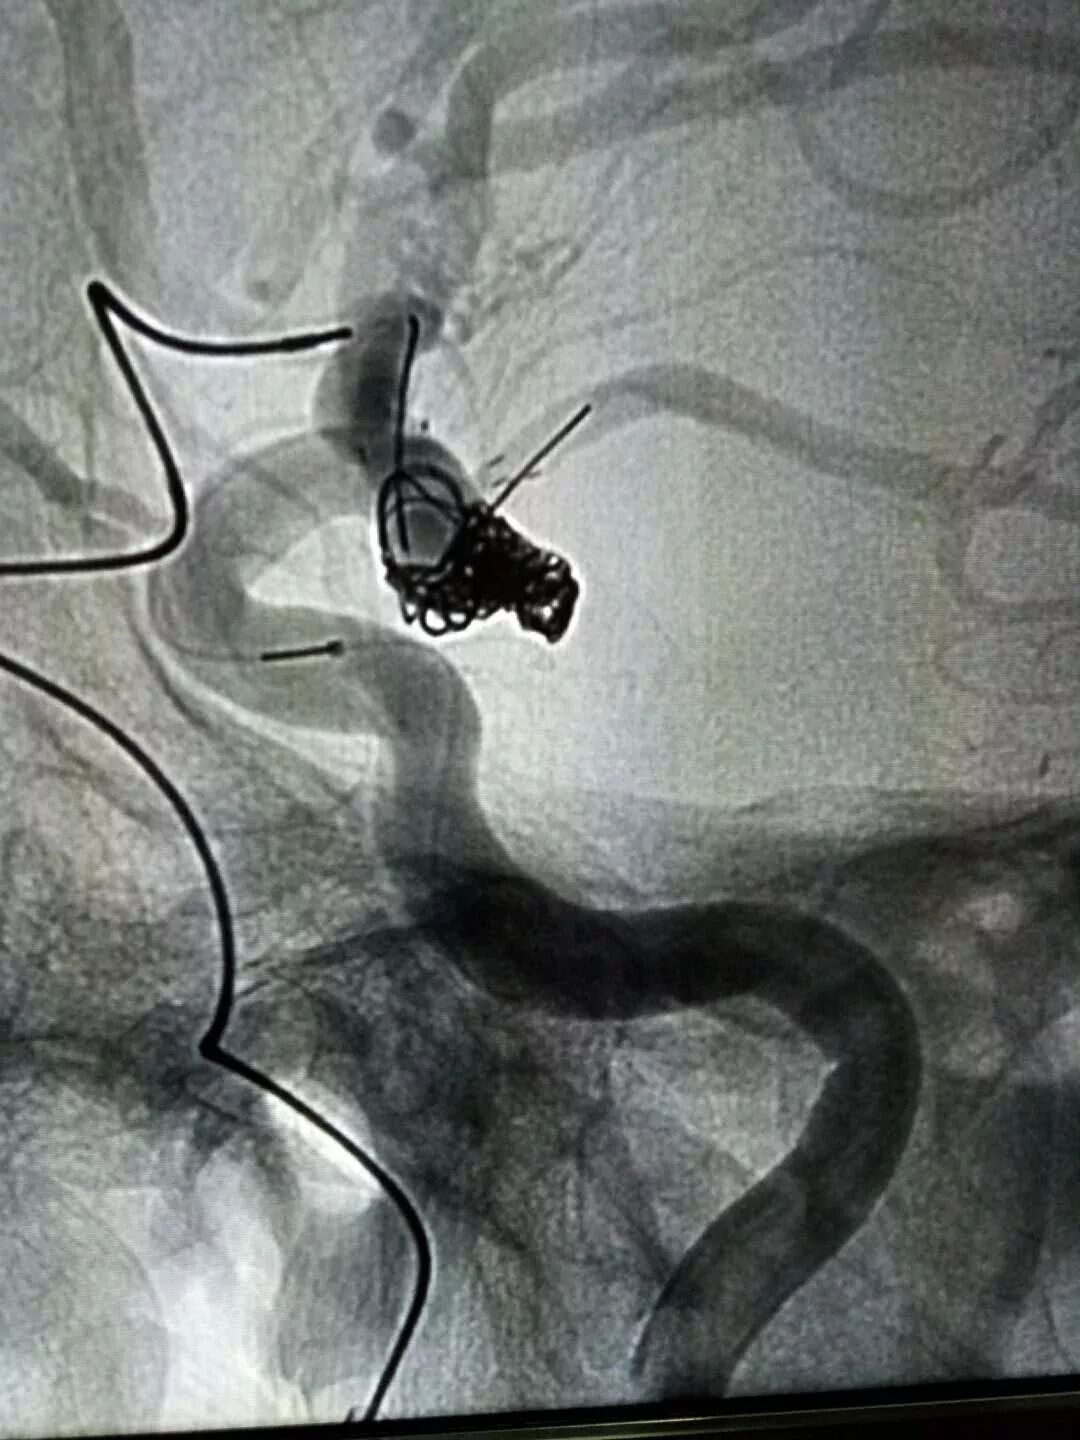

enterprise支架神龙摆尾栓塞胚胎型后交通宽颈动脉瘤